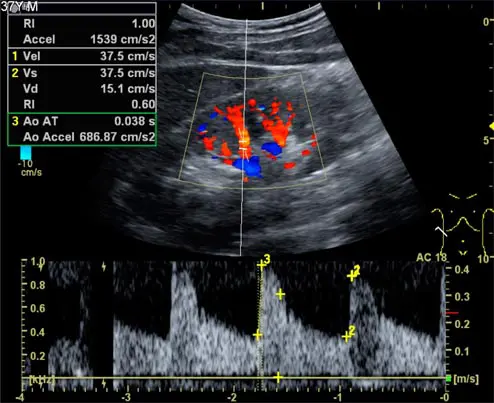

• 경동맥초음파: 목을 지나가는 경동맥 및 추골동맥이 좁아진 정도나 위치, 혈류의 적절성을 확하여 동맥경화증 정도, 혈전의 존재 유무, 뇌졸중의 위험요인 등을 파악할 수 있습니다.

심장초음파

• 심장의 크기와 기능 확인

• 컬러도플러를 이용한 혈류 측정

• 선천적·후천적 심장질환 및 위험요인 모니터링

• 심장 주변의 삼출액, 판막질환, 대동맥하 협착증, 심근병변, 심장종양, 울혈성 심장질환, 대동맥근 질환, 허혈, 심벽의 혈전증 진단